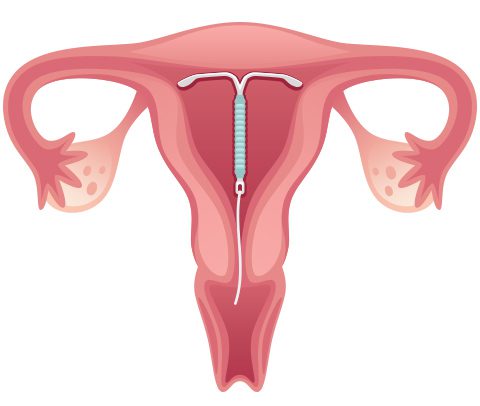

نعم. يحدث بشكل نادر أن يتحرك اللولب داخل الرحم بشكل جزئي أو كامل لدى بعض النساء، وقد لا تلاحظ المرأة ذلك،

مما يؤدي إلى حدوث الحمل.

ويمكن أيضًا أن يحدث الحمل عندما يترك اللولب داخل الرحم مدّة تزيد عن المدة المحددة لاستخدامه الذي حددته الشركة المصنعة، التي تتراوح عادة بين 3 إلى 5 سنوات، وفي بعض الأنواع قد تصل إلى 10 سنوات.

لولب